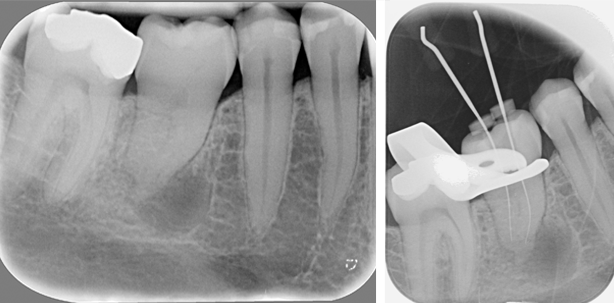

Im Jahre 2014 wurde im Rahmen einer Routineuntersuchung beim Hauszahnarzt eine Röntgenaufnahme des Zahnes angefertigt (Abb. 1). Die Auswertung ergab ein intaktes parodontales Ligament und eine auffällige fast kreisrunde Aufhellung am Apex der mesialen Wurzel. Der Zahn hatte einen Lockerungsgrad 1 und die Patientin berichtete von gelegentlichem Missempfinden.

Es erfolgte die Überweisung an uns zur endodontischen Therapie im November 2014. Am 20.11.2014 wurde die endodontische Initialbehandlung vorgenommen. Unter Lokalanästhesie und nach Legen von Kofferdam wurde zunächst eine Reinigung und Desinfektion des Zahnes und des Kofferdamtuches mit NaOCl vorgenommen. Es folgte die Trepanation und Darstellung der Pulpakammer unter dem Dentalmikroskop. Es konnte zunächst ein mesialer und ein distaler Kanal dargestellt werden. Die Kanäle waren stark obliteriert und wurden nach der Hybridmethode (Hand und maschinell) aufbereitet. Nach elektrometrischen Längenmessungen erfolgte eine Röntgenmessaufnahme zur Bestätigung der Arbeitslängen (Abb. 2). Diese betrugen mesial 16,0 mm und distal 17,0 mm. Im Zuge der Erweiterung der Kanaleingänge konnte mesial schließlich noch ein dritter mesiolingualer Kanal dargestellt werden. Die Aufbereitung endete mit dem Instrument ProTaper Next X3. Es erfolgte eine medikamentöse Einlage mit CaOH und einem temporären Verschluss.

Die Röntgenkontrolle (Abb. 3) zeigt eine wandständige, homogene Wurzelfüllung. Die apikale Aufhellung zeigt sich deutlich weniger hell. Ebenfalls ist die Ausbildung einer spongiosen Struktur im Inneren der Läsion zu erkennen. Der Verschluss der Kavität erfolgte adhäsiv mit dem Nanokomposit Synamel der Marke Cumdente.